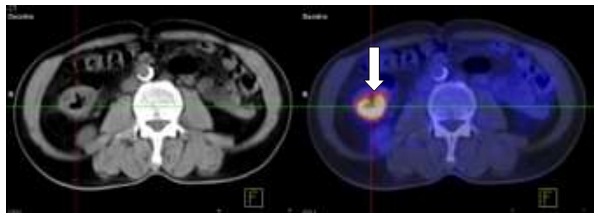

- Chụp PET/CT:

Hình 1.1. Khối đại tràng phải, kích thước: 3x4cm, SUV=7,9.

Hình 1.4. Di căn gan kích thước: 3x4cm, SUV=6,9.